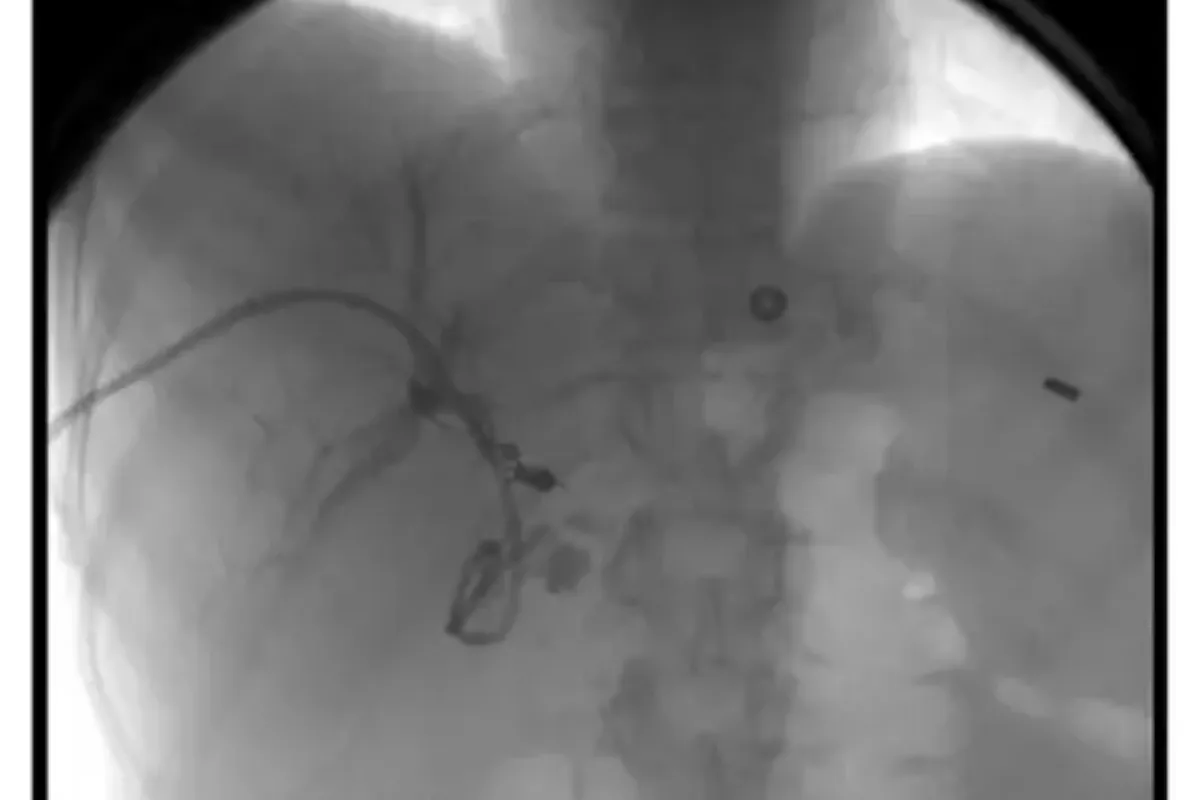

Peripheral Angioplasty procedure at Sarda Vascular Centre Dehradun

Interventional Radiology (IR) uses real-time imaging such as X-ray, ultrasound, CT, or MRI to guide tiny instruments through the body for treatment — without large surgical incisions.